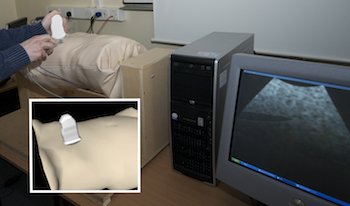

F. P. Vidal, N. W. John, D. A. Gould, and A. E. Healey.

F. P. Vidal, N. W. John, D. A. Gould, and A. E. Healey.

We present an integrated system for training visceral needle puncture procedures. Our aim is to provide a cost effective and validated training tool that uses actual patient data to enable interventional radiology trainees to learn how to carry out image-guided needle puncture. The input data required is a computed tomography scan of the patient that is used to create the patient specific models. Force measurements have been made on real tissue and the resulting data is incorporated into the simulator. Respiration and soft tissue deformations are also carried out to further improve the fidelity of the simulator. Keywords: Physically based modelling, Virtual reality |

Developing an immersive ultrasound guided needle puncture simulator.

We present an integrated system for training ultrasound guided needle puncture. Our aim is to provide a cost effective and validated training tool that uses actual patient data to enable interventional radiology trainees to learn how to carry out image-guided needle puncture. The input data required is a computed tomography scan of the patient that is used to create the patient specific models. Force measurements have been made on real tissue and the resulting data is incorporated into the simulator. Respiration and soft tissue deformations are also carried out to further improve the fidelity of the simulator. Keywords: image guided needle puncture training, interventional radiology training, needle puncture |

This paper reports on a low cost system for training ultrasound imaging techniques. The need for such training is particularly acute in developing countries where typically ultrasound scanners remain idle due to the lack of experienced sonographers. The system described below is aimed at a PC platform but uses interface components from the Nintendo Wii games console. The training software is being designed to support a variety of patient case studies, and also supports remote tutoring over the internet. Keywords: Ultrasound Training, medical virtual environment, hci |